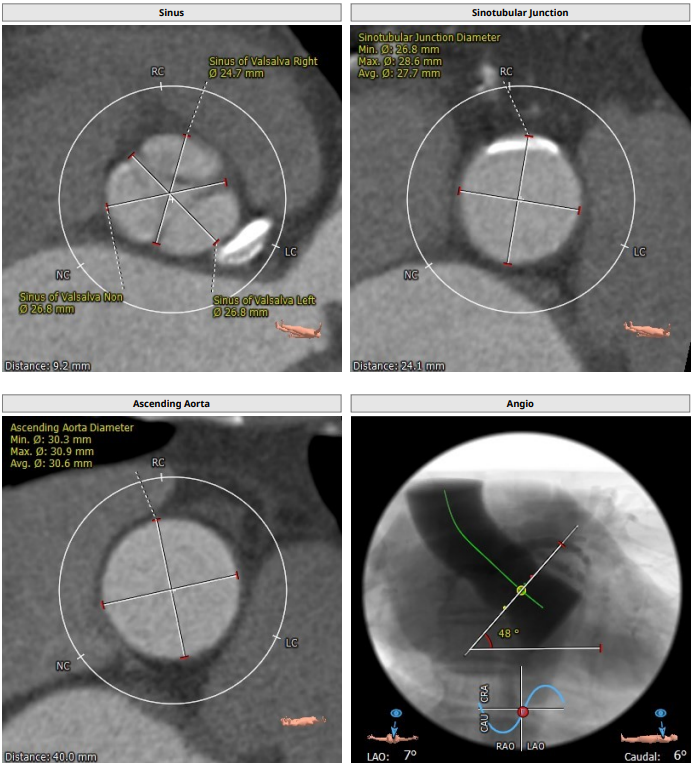

主动脉根部解剖CT影像

钙化积分:221.4mm³。